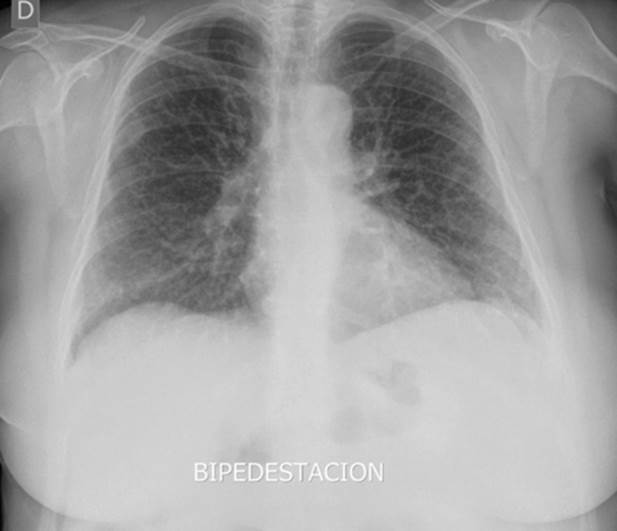

1 mes: radiografía con patrón intersticial bilateral (figura 1) y cultivo (preliminar) con hongo filamentoso. A la auscultación, crepitantes secos bibasales. Se deriva a neumología ante sospecha de neumonitis versus patología profesional.